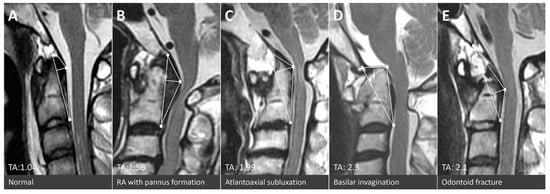

2.2. Radiographical Definition of the Triangular Area of the Cranio-Vertebral Junction (the TA of the CVJ)

| Triangular area (cm2) | 1.05 ± 0.26 | 0.96 ± 0.31 | 1.58 ± 0.47 | <0.001 | |||

| pathology | Atlantoaxial subluxation | Basilar invagination | Odontoid fracture | Os odontoideum | |||

| n | 90 | 3 | 31 | 5 | |||

| Triangular area (cm2) | 1.54 ± 0.42 †,‡ | 1.84 ± 027 †,‡ | 1.62 ± 0.56 †,‡ | 2.15 ± 0.62 †,‡ | |||